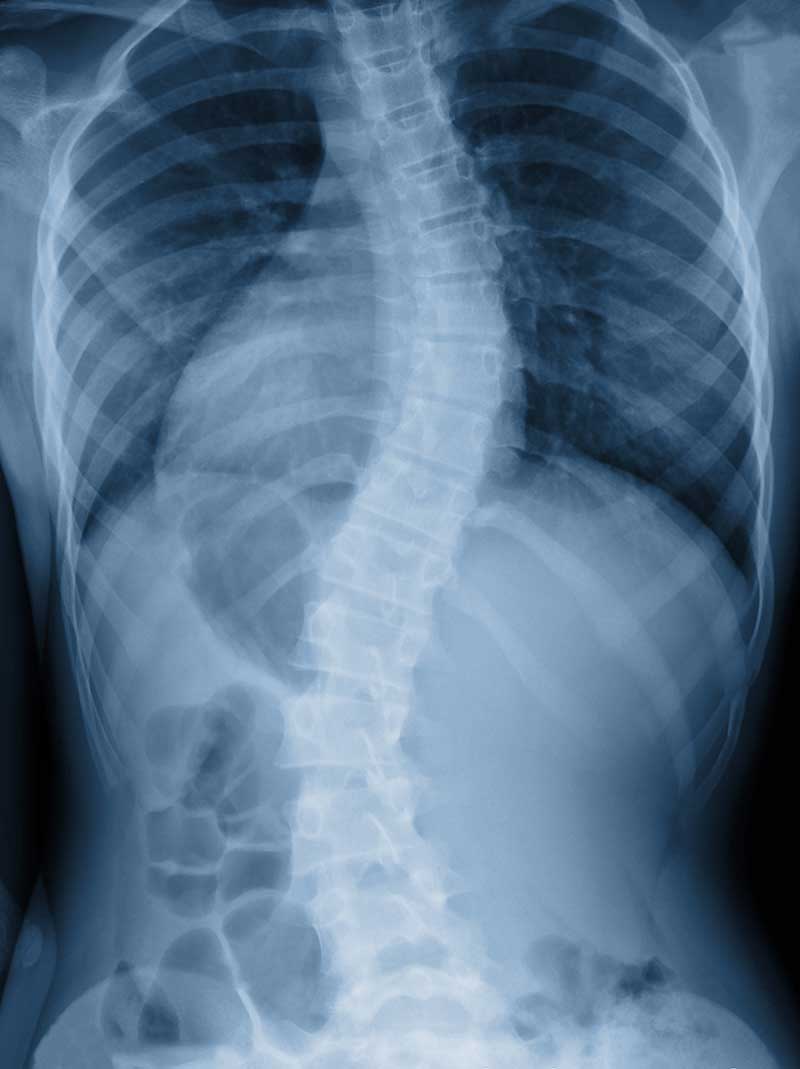

Parents or loved ones are often the first to notice scoliosis, especially when the shoulders or pelvis appear uneven. A physical examination will assess the individual’s gait and visually inspect the spine for any curvature. One test commonly used is the Adams Position Test, where the patient bends forward to see if a curve is present. If a curvature is noticed, an X-ray will be performed to determine the severity of the condition.